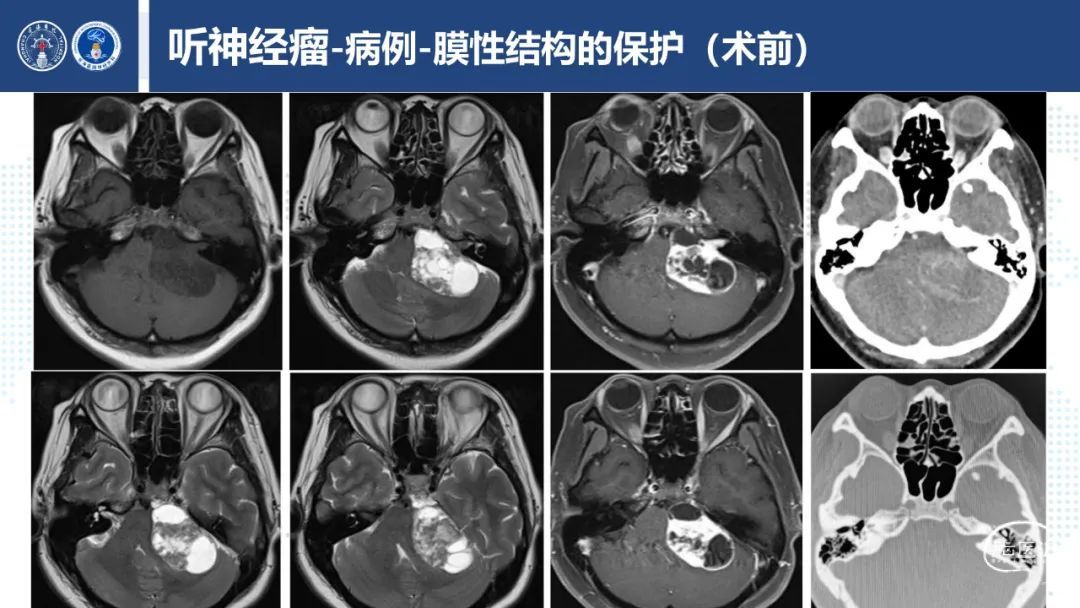

听神经瘤,是起源于前庭神经鞘膜的肿瘤,围绕连接内耳、大脑平衡和听觉神经间生长。听神经瘤虽是一种良性肿瘤,生长缓慢,但与周围三叉、面听、外展神经、AICA、PICA和脑干等重要结构关系密切,如果肿瘤巨大,常造成相应的神经功能缺失,严重影响患者生活质量,甚至压迫脑干、造成脑积水而危及生命。